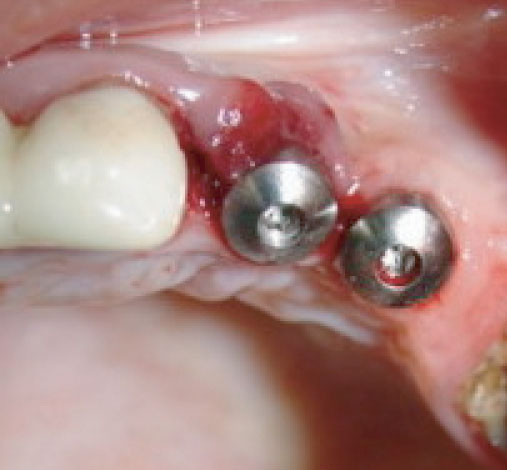

Foto 4: Retiramos los pilares de cicatrización, habiendo madurado el tejido alrededor de estos y se procedió a la conexión de dos pilares Multi-Unit de 1mm de altura cada uno.  Torquímetro manual con apriete a 32 Ncm.

Foto 11: Prótesis sobre implantes atornillada en zona 23 y 24.

Resumen